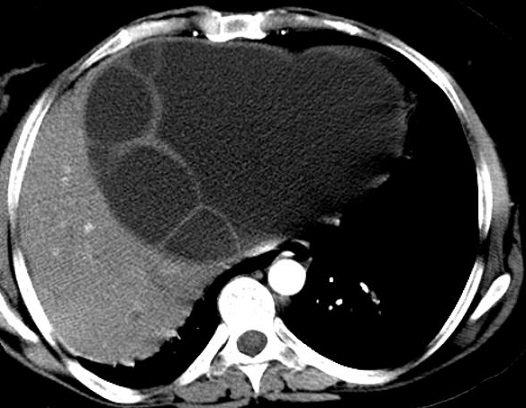

Image TDM

de abces du foie : Aspect TDM de abces du foie est

variable : lesion en apparence peripherique de hyperdensite

et a central hypodense s'observe souvent dans abces amibien . Ce qui peut en presence de

gas ( 20% de gas ) . Aspect en cloisone ou multiple

loculaire , bien definie " cluster sign" peut

se retrouve dans l'abces a pyogenes. En cas de TDM

plus de contrast intraveineuse , image de double de cible "double

target sign" peut en voyait .

Aspect radiologique TDM d'une abces

a pyogenes multi loculaire du foie en realisee sous forme de

grappe "cluster sign " . |

|

Image TDM d'une abces du foie en coupe

coronale . Aspect de la lesion est hypodense

multi loculaire se situe au foie gauche . Image

radiologique TDM encoupe coronal , aspect

radiologique en susgeste du abces a pyogenes |